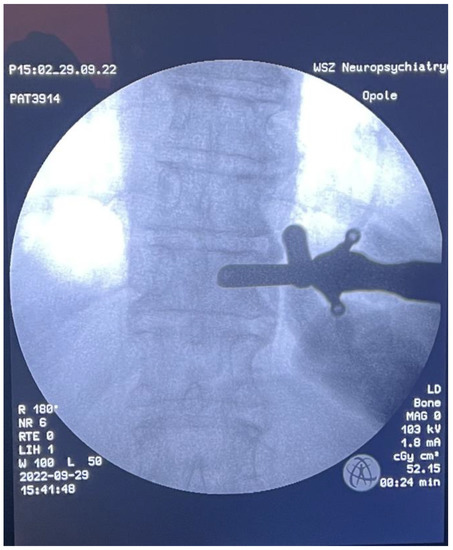

Fully Endoscopic Spine Separation Surgery in Metastatic Disease—Case Series, Technical Notes, and Preliminary Findings